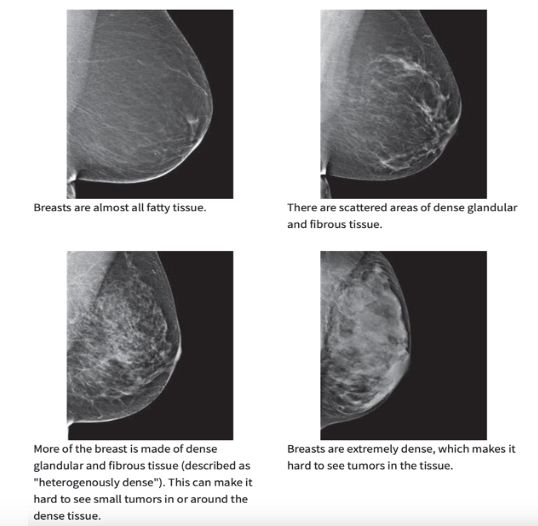

The reason behind why they tell us to wait until after 40 (or some say even after we’re 50) is because of the density of our breast tissue. It is very common in women under 40 to have dense breast tissue. Well, mammograms have a decreased sensitivity as low as 48% in women with dense breasts (4)!! Take a look at this image, which does a great job of showing why.

The top left is almost all fatty tissue. The breast to the right has some scattered areas of dense tissue. Under that to the left shows a breast where a lot of the tissue is dense. And then to the right you see extremely dense tissue. Since both dense tissue AND tumors show up as white on a mammogram you can see how it could be very difficult to see tumors in between all the dense tissue. The problem is that over half of women under the age of 50 have dense breast tissue. Over half!!! That is a huge number! Then we have 40% of women in their 50s who also have dense breast tissue and 25% of women in their 60s(5)!! So, even for those who have reached the age where mammograms are now recommended, it’s not like something magical happens once you turn 40 then all of a sudden everyone’s breast tissue is no longer dense! If you are someone who does receive mammograms then be sure to ask your radiologist about the density of your breast. They should tell you. As a matter of fact, in 38 states now it is mandatory for radiologists to send a letter home informing women with dense breasts that their mammogram is likely to not be as effective so that they can decide if they would like to opt in for different types of screening methods. Check the image below to find out if your state is one of the many that require notifications of the density of your breast tissue. Even if your state is not one of the many, it is still a good idea to ask as knowledge about your own body will serve you well in life.